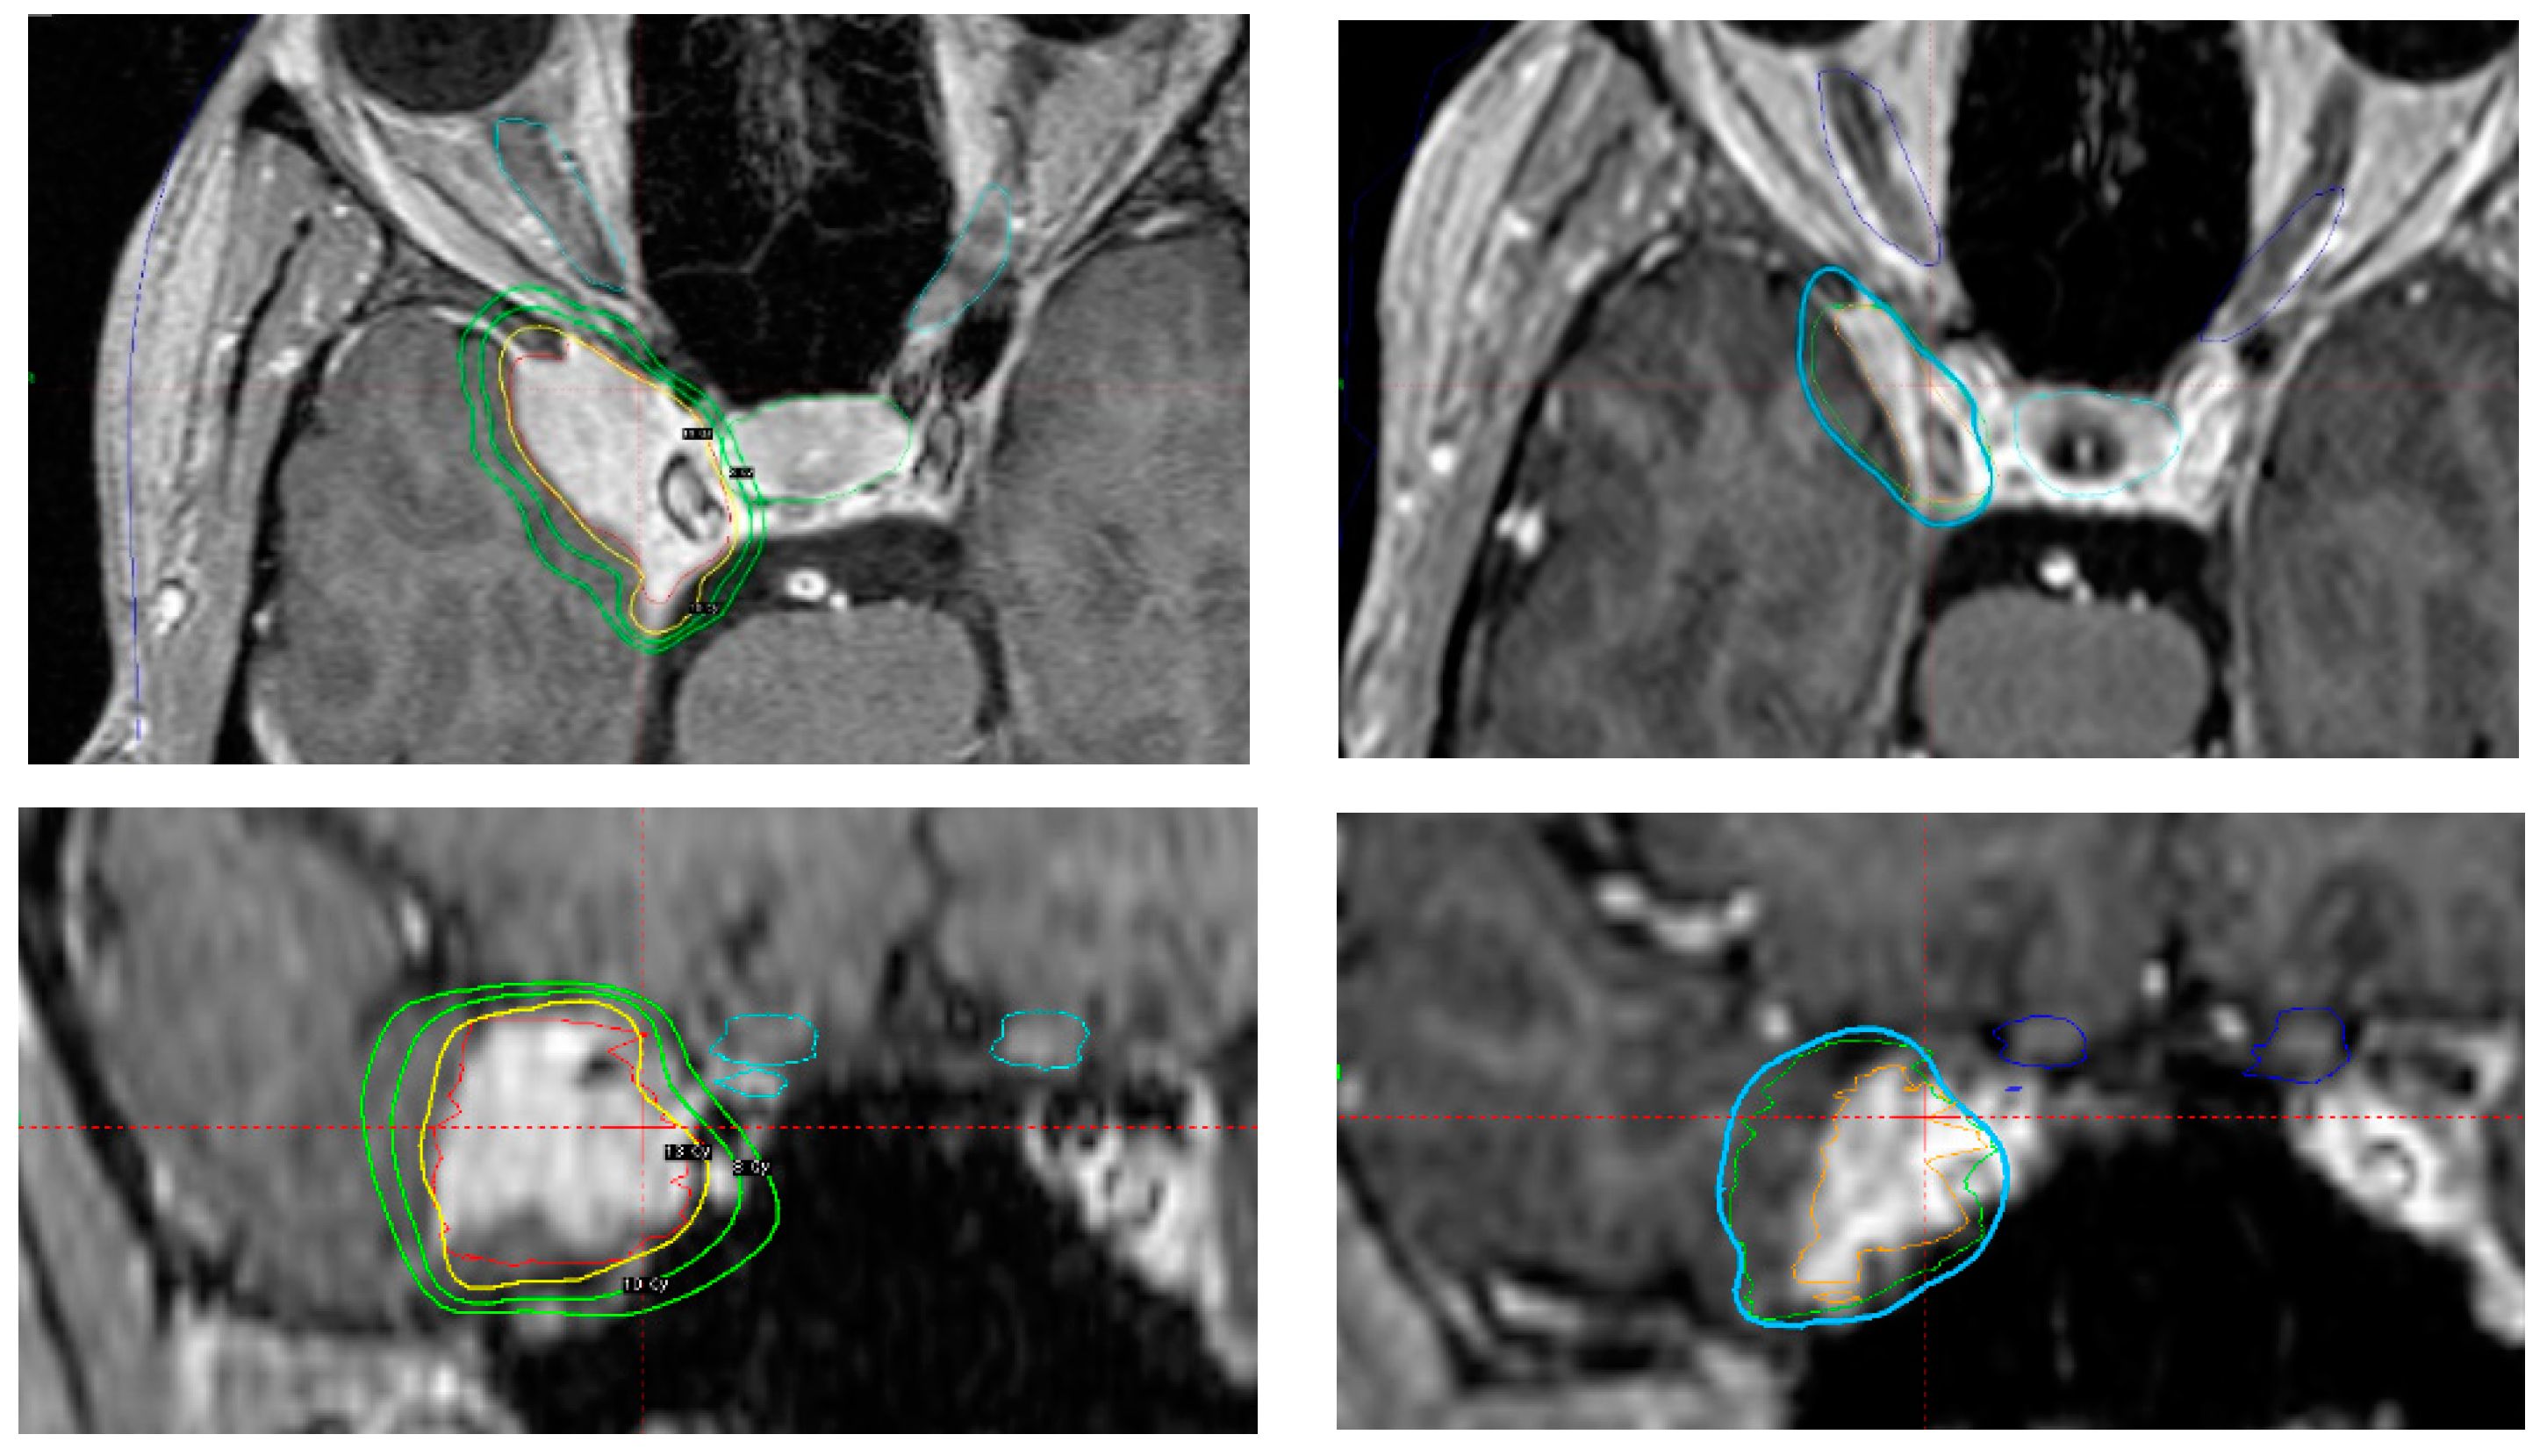

Figure 5.

Axial and coronal contrast-enhanced MRI-based treatment (left

top and bottom) and imaging follow-up 9 years and 6 months after treatment (right top and bottom). Imaging-defined CSM treated in a 44 year-old woman reporting right periorbital dysesthesia. No further neurological defi cits. No previous surgery. In order to avoid future tumour-associated complications due to the eloquent location, definitive SRS was performed with 13 Gy prescribed to the 65% isodose line. After a follow-up of 114 months, target volume decreased from 5.65 cc to 2.38 cc. The patient developed no new neurological deficits and the periorbital dysesthesia had regressed.